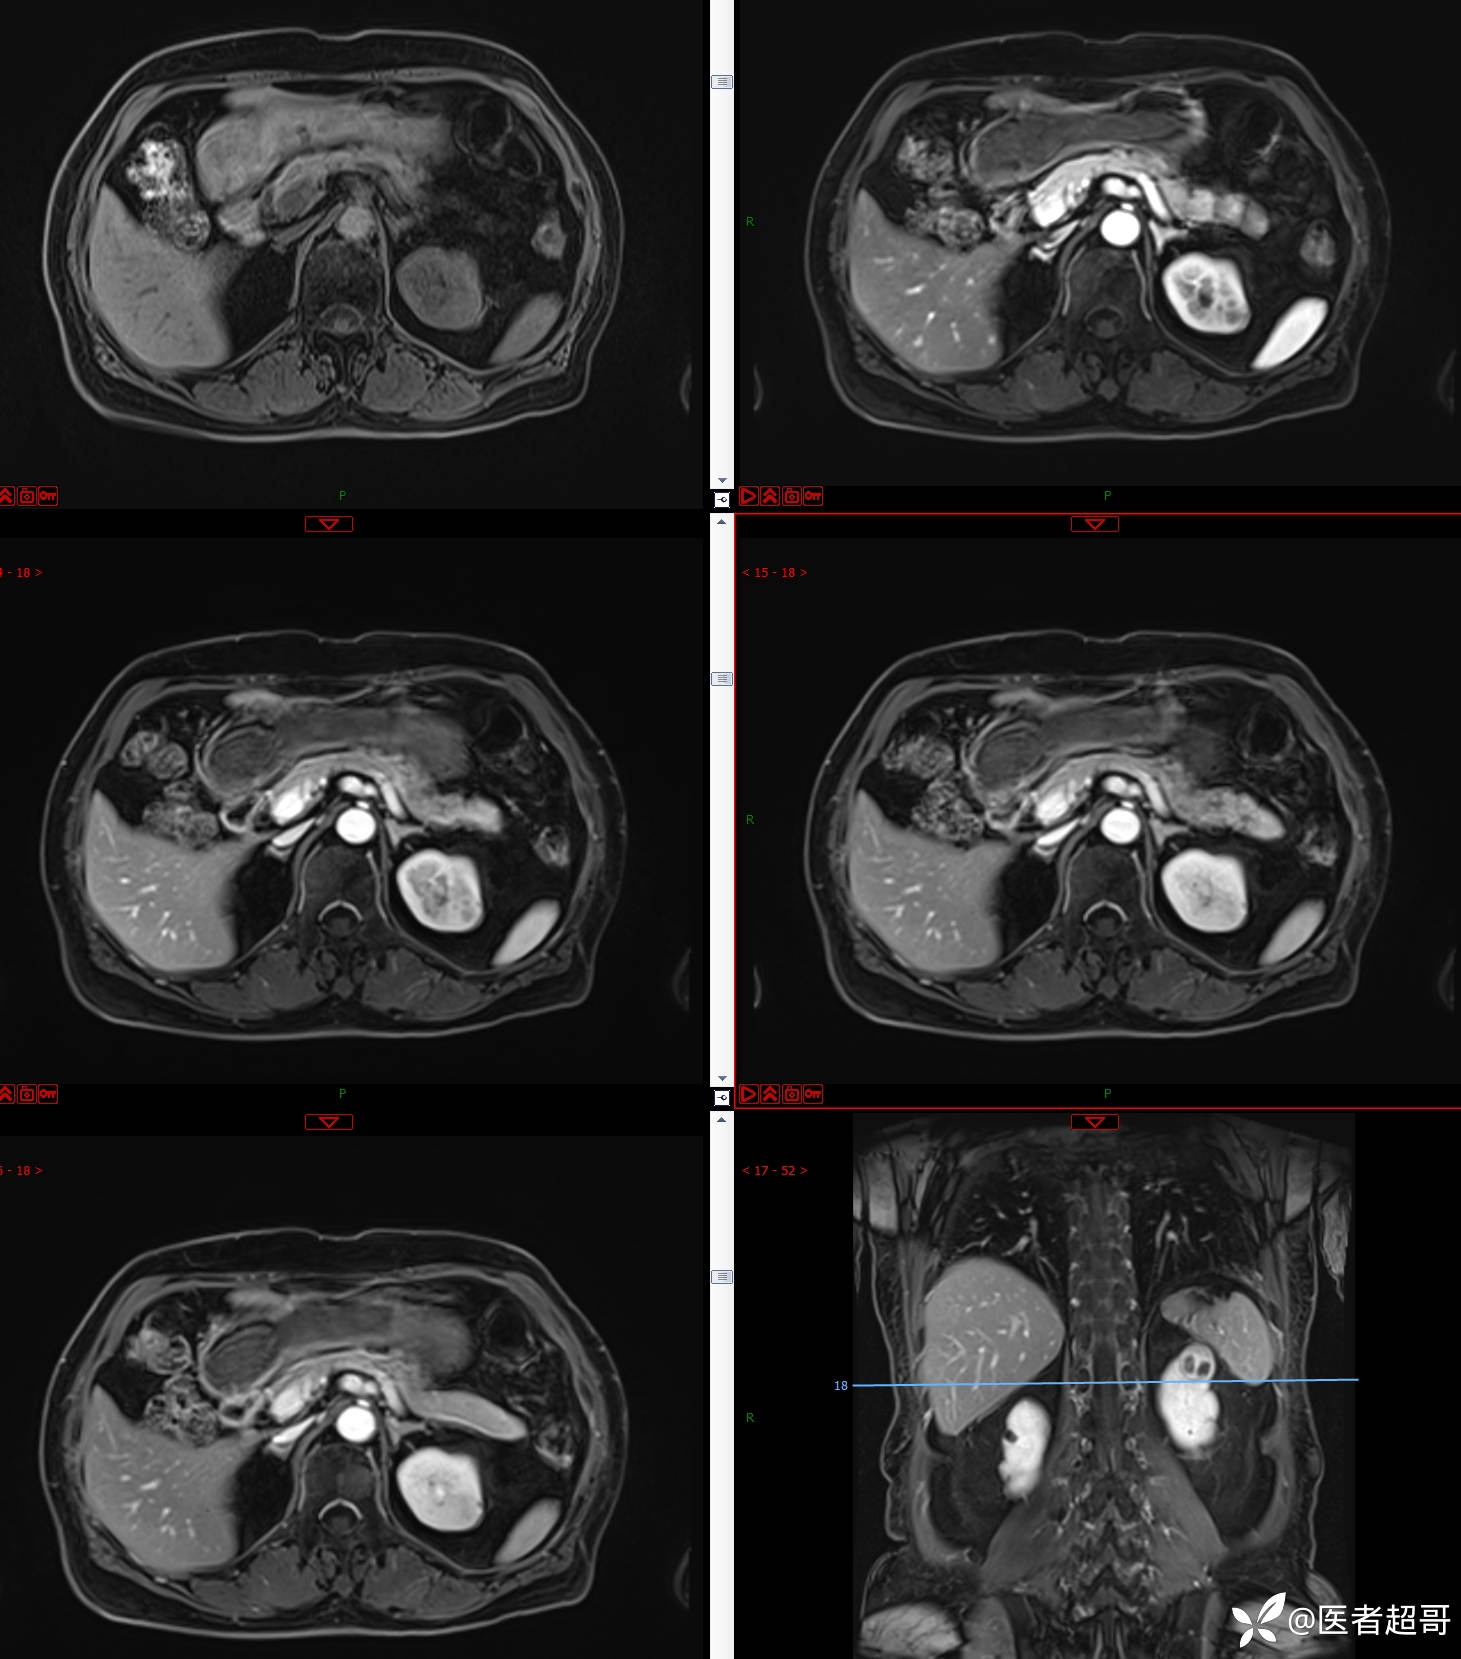

左肾占位2个月就诊,有病理,请分析!

主 诉:查体发现左肾占位2月。

现病史:患者自述2月前于镇中心卫生院行腹部超声发现:左肾实性占位。患者无尿频尿急尿痛,无发热寒战,无恶心呕吐。未行特殊治疗。现患者为求进一步诊治,就诊我院,门诊以“肾肿物”为诊断收入院,患者自发病以来,神志清,精神可,饮食可,睡眠一般,大便正常,体重未见明显改变。